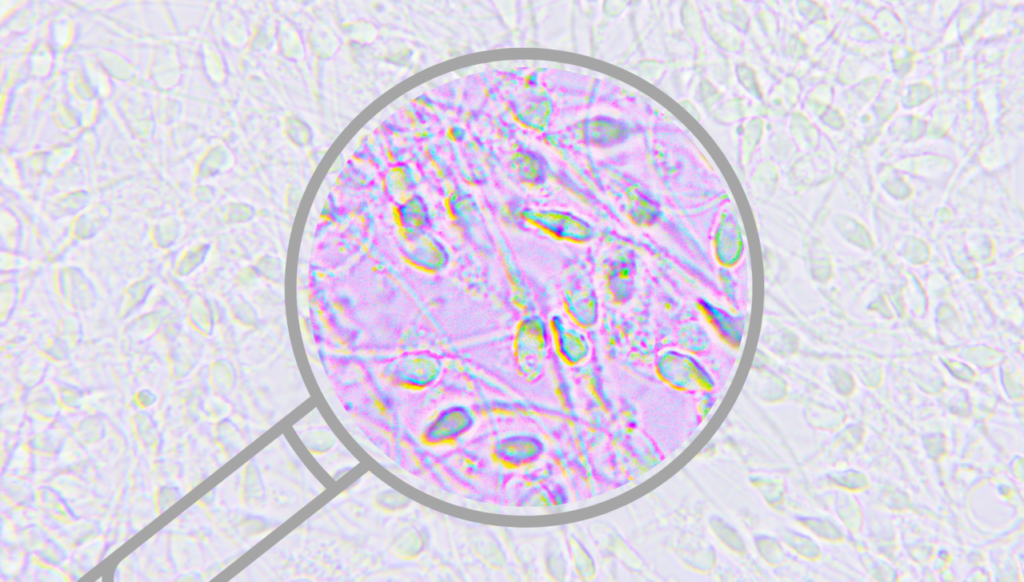

Badanie nasienia (spermiogram, seminogram) to test diagnostyczny, który polega na dokładnej makroskopowej i mikroskopowej ocenie próbki ejakulatu pod kątem jej właściwości fizykochemicznych (kolor, konsystencja, pH, skład) oraz obecności, wyglądu i ruchliwości plemników. Jest to podstawowe badanie płodności mężczyzny, które przeprowadzane jest w laboratorium medycznym lub w klinice leczenia niepłodności. Jest ono bezinwazyjne i całkowicie bezbolesne.